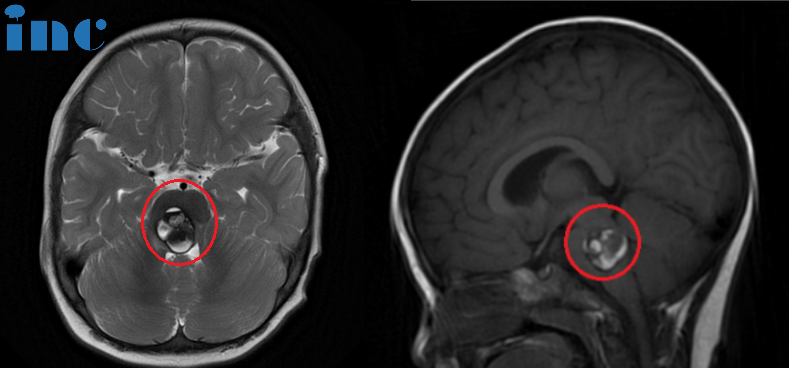

▼术前术后对比图片

术前:脑桥占位。双眼斜视、畏光,面瘫,频发不自主扭头动作,走路稍有不稳。头颅MR(红色区域)显示:脑桥血肿,可见16 x 22 x 21mm肿块,四脑室受压变窄。

术后:头颅MR(蓝色区域)显示小脑半球及脑干形态正常,中线结构居中,原脑桥内团块状信号消失。